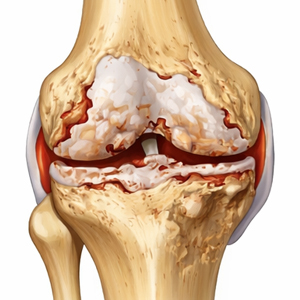

Arthrose ist kein rein mechanischer Verschleiß – sie ist ein komplexer, biologisch aktiver Prozess.

Was ist Arthrose?

Arthrose ist eine degenerative Erkrankung des Gelenkknorpels.

Im Verlauf kommt es zu einem fortschreitenden Abbau der Knorpelstruktur, Veränderungen des Knochens unter dem Gelenknorpel sowie entzündlichen Reizreaktionen der Gelenk-Innenhaut.